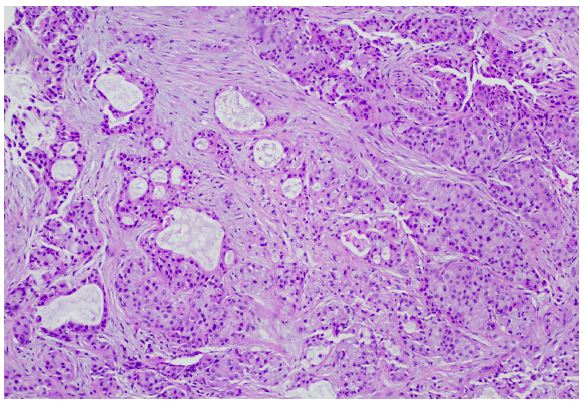

Concordance with the lung adenocarcinoma confirmed that the breast lesion was consistent with metastatic lung cancer (GATA-, mammoglobin -, TTF-1+, Napsin A+, SOS-10+). Staging PET/CT scan revealed no uptake in the lung, minimal uptake in the right breast lesion and a concerning lesion at L3. MRI of the brain was negative for intracranial metastatic disease.

An interventional radiology vertebral biopsy revealed metastatic adenocarcinoma diffusely positive for CK7, TTF-1 and Napsin A consistent with the lung primary (ER and GATA3 negative; Figure 3).

Figure 3: Bone biopsy histology. (a) Adenocarcinoma infiltrating within the bone marrow (100x).

Histologic analysis and immunohistochemical evaluation of breast lesions can differentiate between primary and metastatic disease. In the case presented here, the IHC of the breast lesion indicated low ER expression with absent PR and Her-2, negative GATA3 [5] and mammaglobin [6], inconsistent with a breast primary; the positive expression of TTF-1 and Napsin A, characteristic of 75% and 84% of lung adenocarcinomas, respectively [7,8] suggested lung origin. While TTF-1 is one of the most commonly utilized IHC markers in the diagnosis of lung cancers, it is also able to distinguish primary lung adenocarcinoma from tumors of other sources, substantiating the breast and spine lesions as lung metastases [9,10].